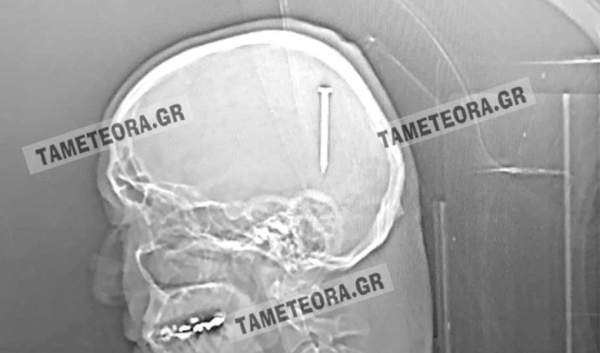

Απίστευτο περιστατικό στην Καλαμπάκα: Σφηνώθηκε καρφί στο κεφάλι άνδρα

Αν το καρφί βρισκόταν ελάχιστα χιλιοστά από το σημείο που σφηνώθηκε, θα ήταν πολύ επικίνδυνο